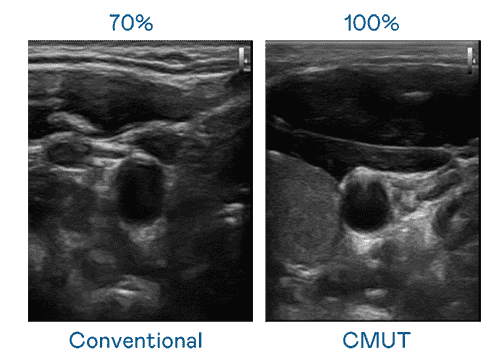

CMUT 技术是一种用电容式微机电元件来产生超音波讯号的技术。。。。与传统 PZT 压电式技术相比,,,CMUT 频宽增加 30%,,,更宽频的超音波讯号让影像解析度大幅提升,,,,是实现高影像品质医疗超音波扫描、、、促进精准医疗发展的关键技术。。。。

大频宽带来超清晰影像

超音波影像的解析度高低,,首先取决于探头能发出的讯号频宽。。。。牛牛游戏 CMUT 可提供高清晰的超音波讯号,,提供高频宽、、、、高灵敏度、、、影像纹理细节更高的超音波影像,,,协助医护人员缩短影像判读时间及利用精准的医疗影像进行诊断。。。